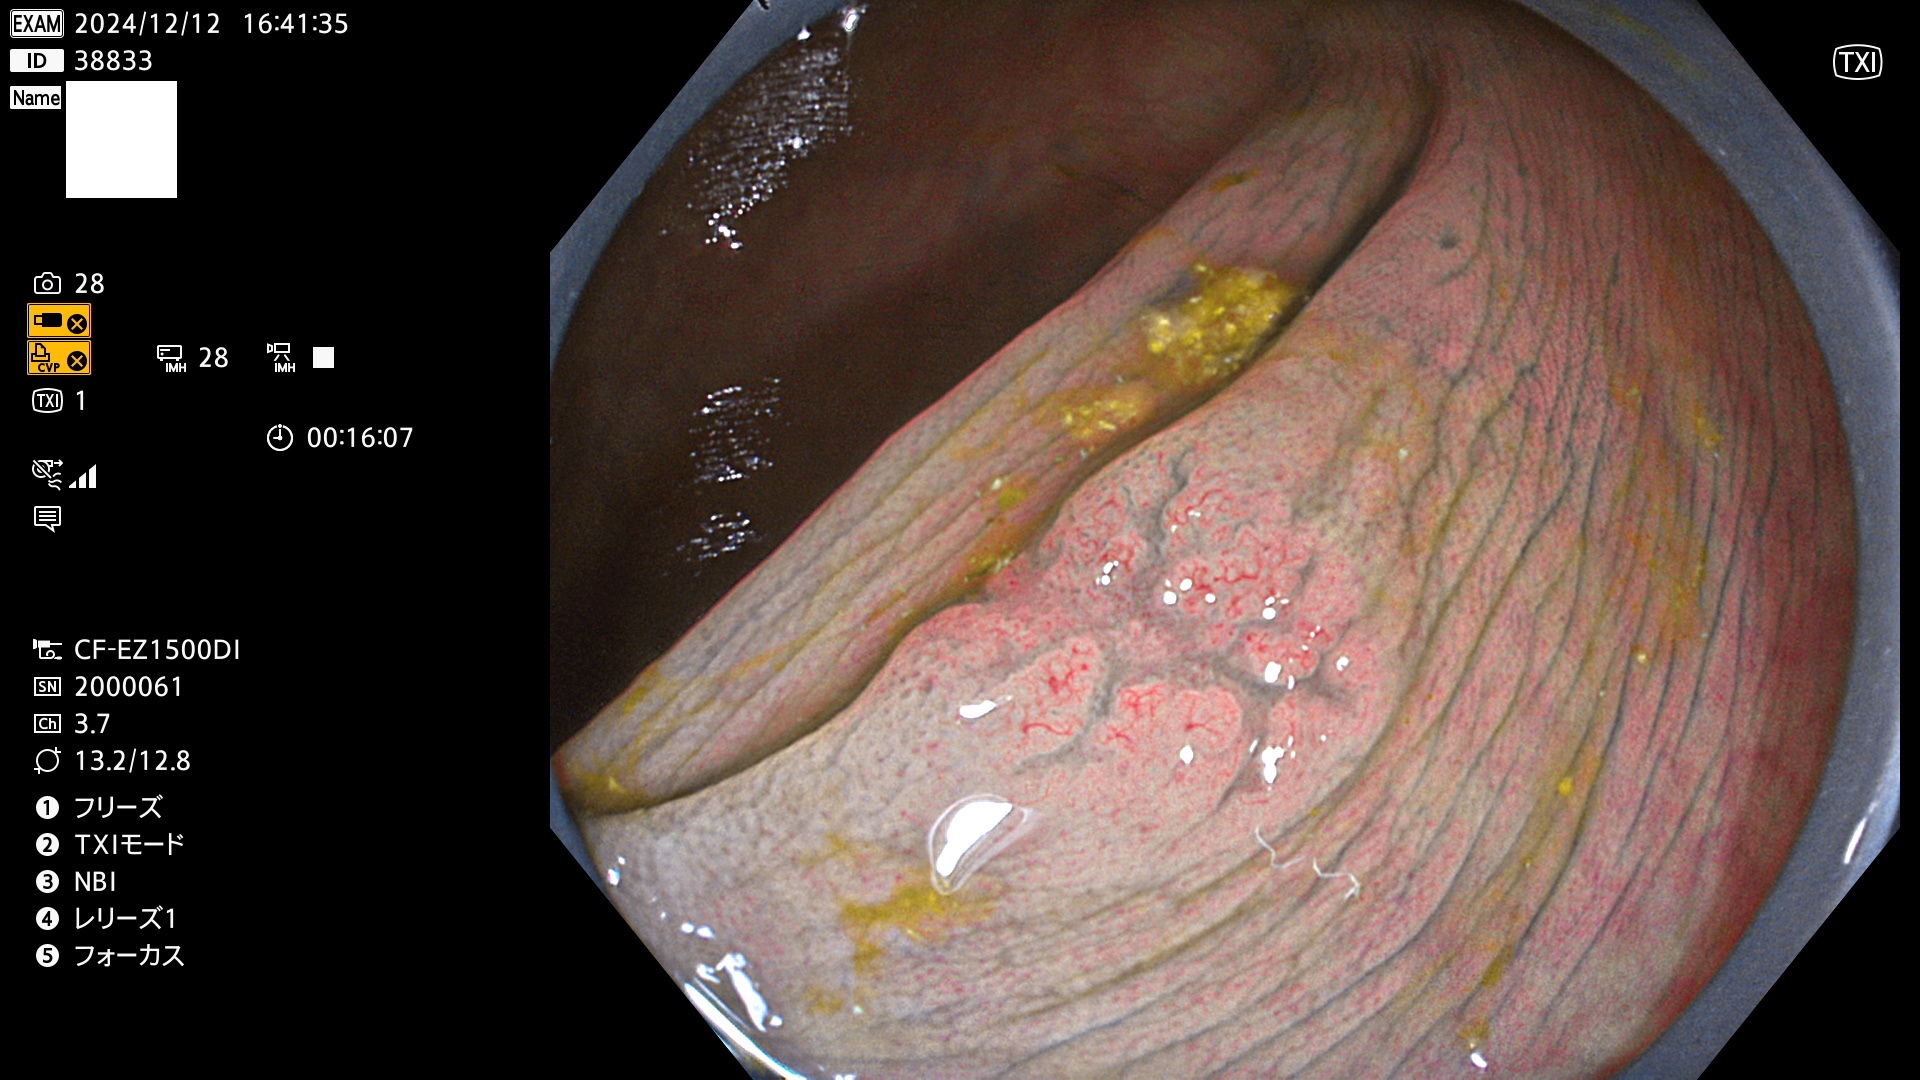

完全に平坦な物をUb、陥凹している物をUcと呼びます。最も発見が難しく危険な病変です。

専門的)何故、陥凹していると危険? 癌遺伝子の変異が蓄積すると細胞分裂が盛んになり隆起するのでは?と通常は思われるでしょう。しかし実際は逆です。これは2022年の記事にある「細胞はストレスに直面したら細胞分裂を止める(細胞老化に入り休眠する)という生命の基本的現象」によるものです(Oncogene Stress)。細胞老化を起こすのが癌抑制遺伝子で、この安全装置(ブレーキ)が壊れると癌になります(休眠からの覚醒)。ですから陥凹は「まだ癌では無いが癌化の直前」を意味します。特に「小サイズなのに陥凹している」病変は短期間に腫瘍進化(IntraTumor Heterogenity⇒2021年記事)が起きたことを意味します(=ゲノム不安定性

毎週の検査(木・金・土・日)に発見されたUb、Uc型・腺腫を、その週の日曜の夜にUPし1週間、提示します。

抽出の対象期間 2024年12月12日〜12月16日の5日間(60件の検査)13件 (13/60=21%)